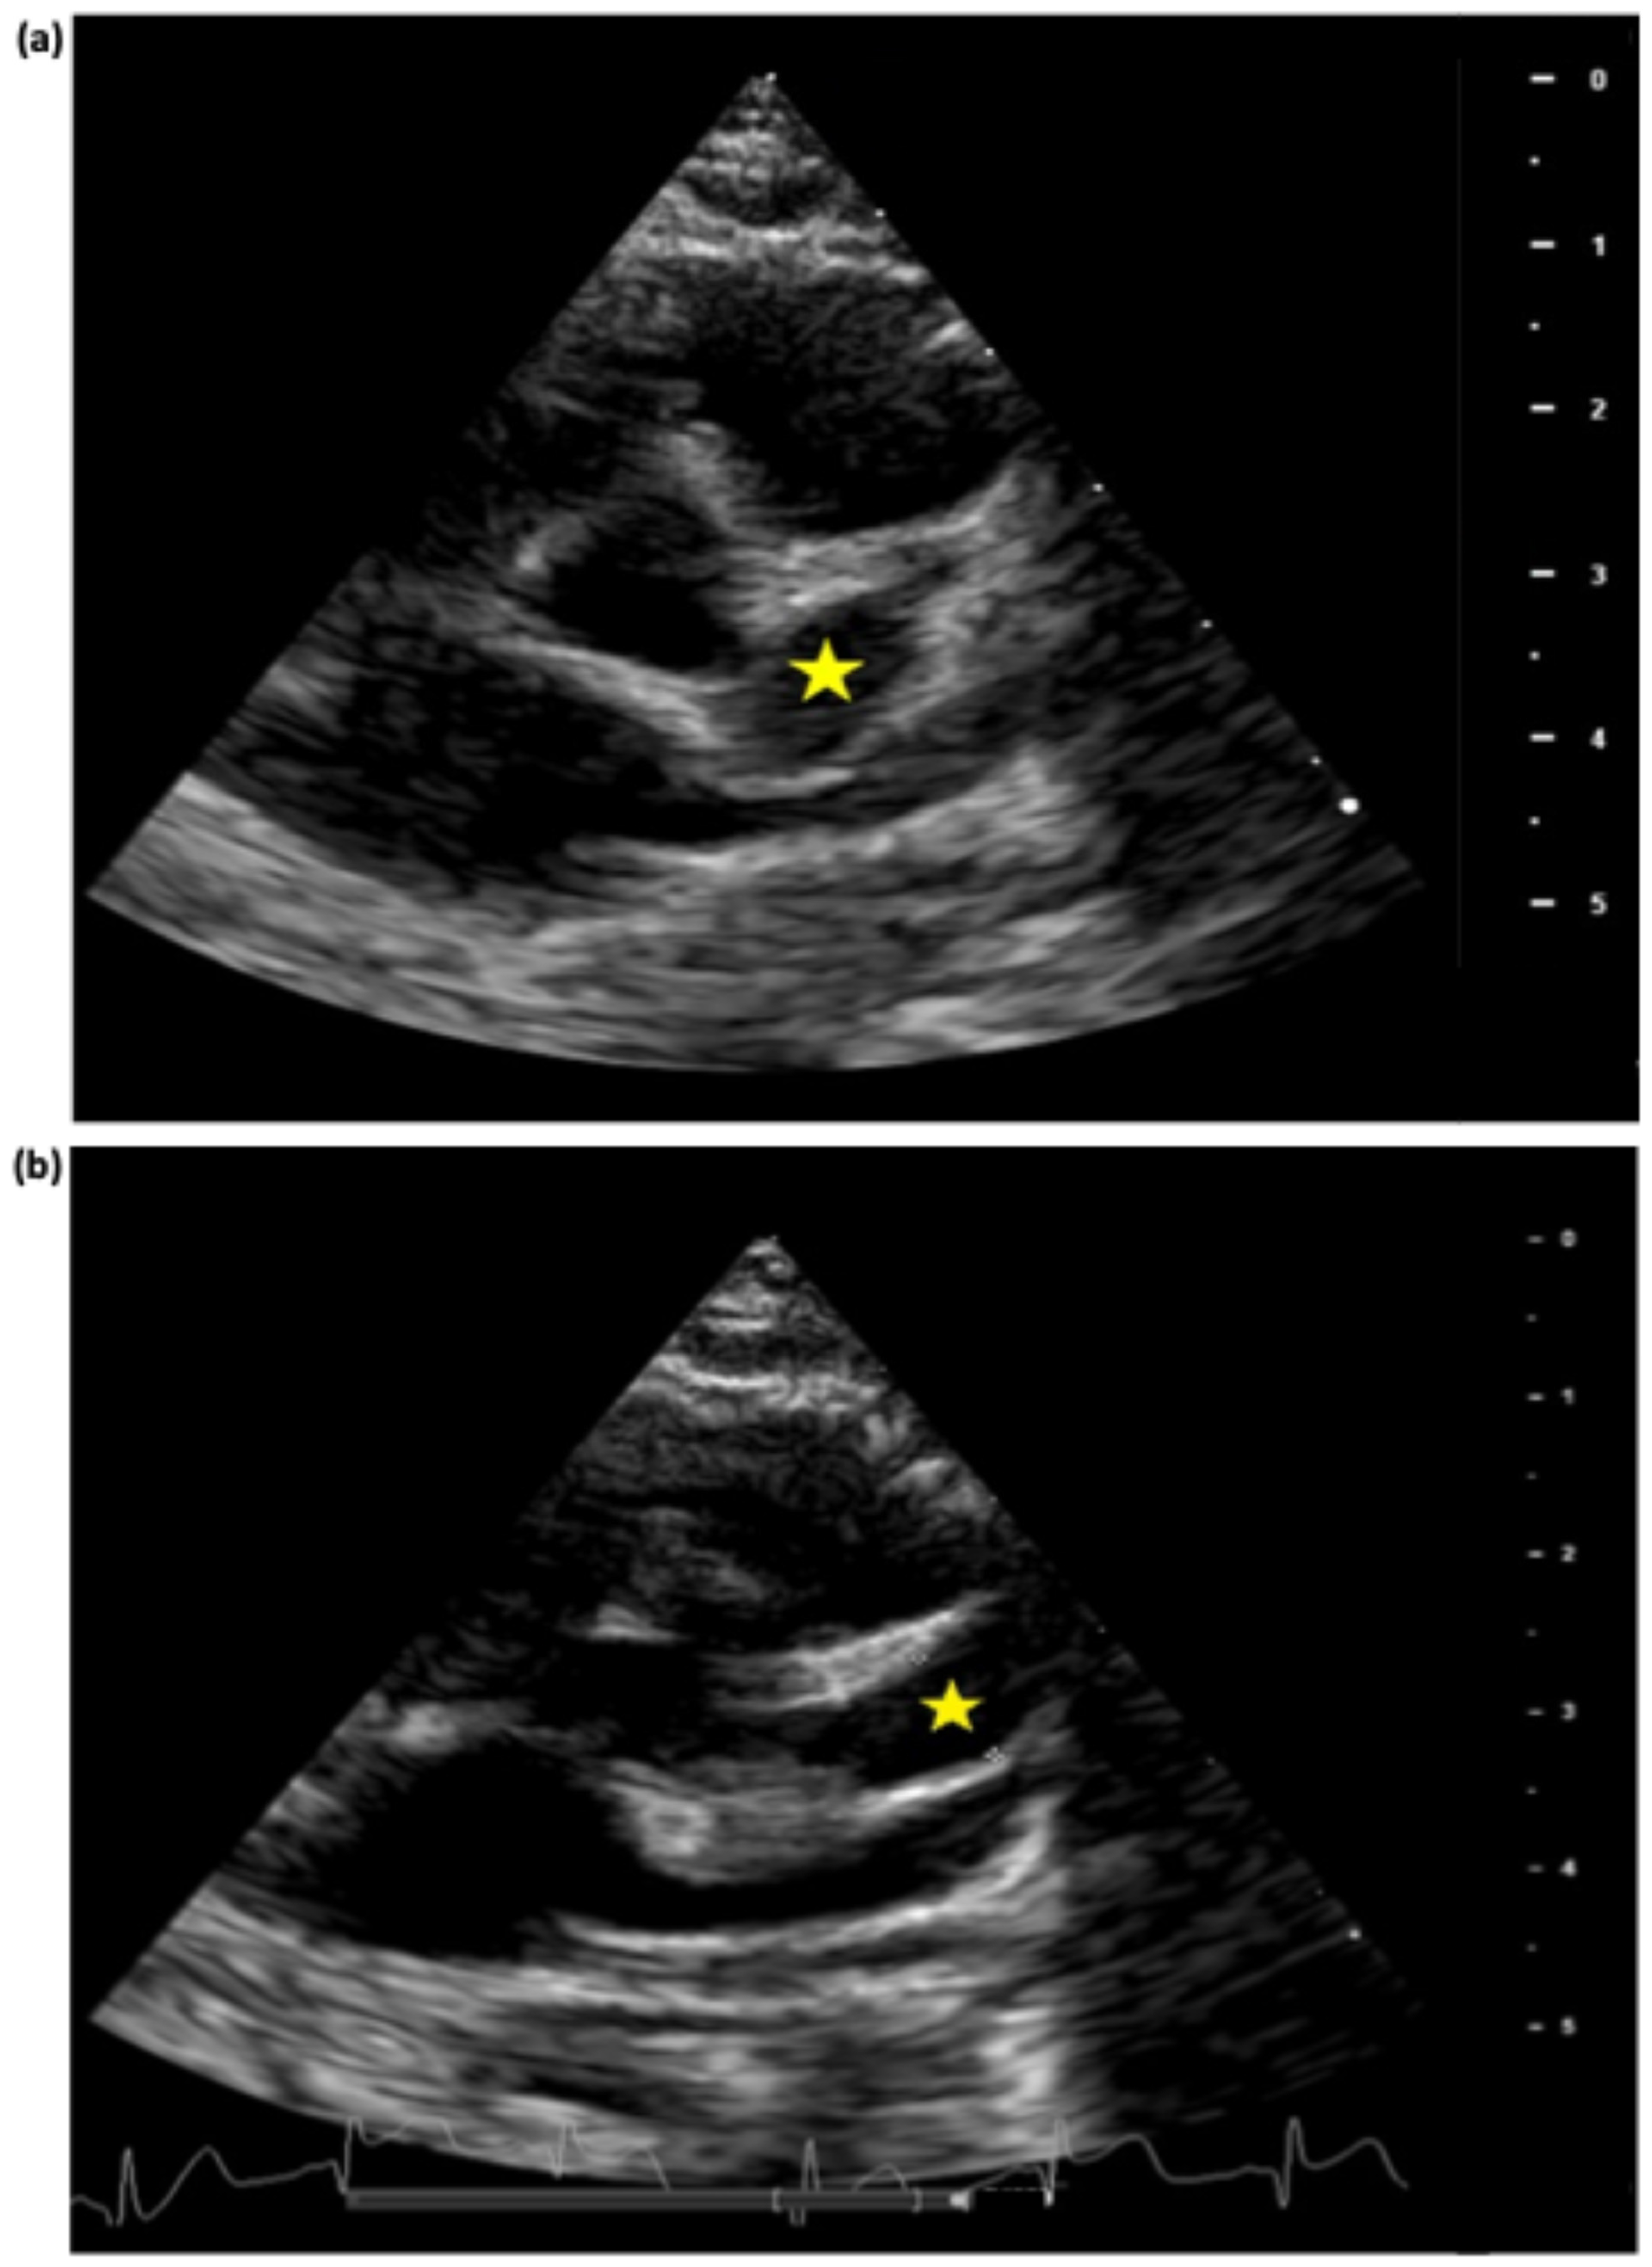

| LMCA | Ø | 1st 4 mm (z-score +5.8) | 1st 4.2 mm (z-score +6.4) | 1st 4.5 mm (z-score +7.2) | 1st 4 mm (z-score +5.8) | Ø | Ø | Ø |

| Ø | 2nd 6 mm (z-score +11.4) | 2nd 5.3 mm (z-score +9.4) | 2nd 5.5 mm (z-score +10) | |||||

| LAD | 1st 4.2 mm (z-score +12) | 1st 5 mm (z-score +16) | 1st 5.5 mm (z-score +18) | 1st 5.5 mm (z-score +18) | 1st 5.5 mm (z-score +18) | 1st 5.4 mm (z-score +17.8) | 2 aneurysms max diameter 4.5 mm (z-score +13.7) | 1st 3.6 mm (z-score +9.6) |

| Ø | 2nd 4.4 mm (z-score +13) | 2nd 7 mm (z-score +25) | 2nd 7.5 mm (z-score +27) | 2nd 6.8 mm (z-score +24) | 2nd 6.6 mm (z-score +23) | Ø | ||

| Ø | Ø | 3rd 6 mm (z-score +20.5) | 3rd 6 mm (z-score +20.5) | Ø | Ø | Ø | Ø | |

| RCA | 1st 3.1 mm (z-score +5.5) | 1st 5.2 mm (z-score +12.5) | 1st 5.5 mm (z-score +13.5) | 1st 6.8 mm (z-score +17.8) | 1st 7 mm (z-score +18.5) | 5.4 mm (z-score +13) | Max diameter 3.4 mm (z-score +6.5) | 1st 3.5 mm (z-score +6.8) |

| Ø | 2nd 3.2 mm (z-score +6) | 2nd 4.1 mm (z-score +8.8) | 2nd 3.9 mm (z-score +8) | Ø | Ø | Ø | Ø | |